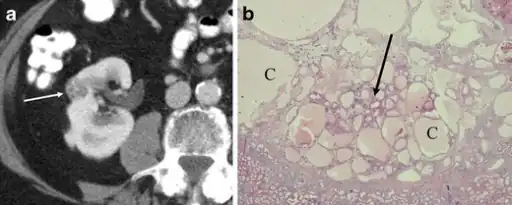

a,b)Renal oncocytoma with cystic change.